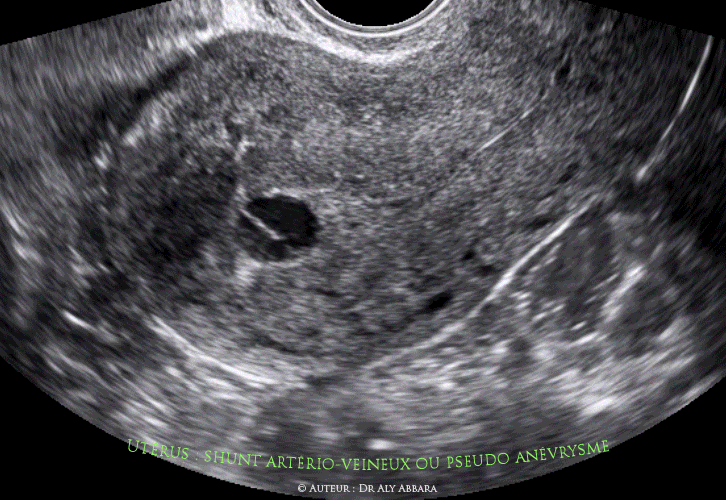

- Anomalie vasculaire utérine de type " shunt artério-veineux ou pseudo anévrysme " mis en évidence deux semaines après une révision utérine (par simple aspiration) pour rétention trophoblastique de 10 cm3 suite à un avortement incomplet (6 semaines auparavant) d'une grossesse de 8 SA.

- Ce shunt artério-veineux a été mis évidence fortuitement, lors de la consultation post-opératoire d'une révision utérine par aspiration réalisée deux semaines auparavant. Patiente sous contraception estroprogestative. Les premières règles post opératoire n'ont pas eu lieu encore.

- L'échographie met en évidence la présence, au font de la cavité utérine, d'une formation arrondie, anéchogène, partiellement cloisonnée avec un liquide aux mouvements tourbillonnants. Le Doppler couleur montre qu'il s'agit d'une pathologie vasculaire débutant dans la cavité utérine et traversant verticalement le tiers de l'épaisseur myométriale profonde.

L'analyse du spectre-Doppler est en faveur de flux artériels tourbillonnants et se connectant à la circulation artérioveineuse située dans la couche profonde du myomètre.